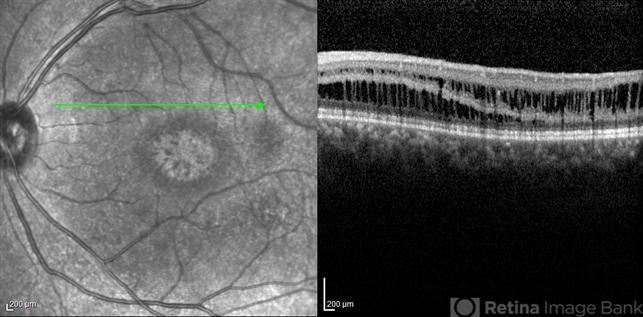

- optical coherence tomography (OCT), juvenile retinoschisis, macular schisis

- Shabnam Pooreh, Negah Eye Center, Tehran , Iran

Optical coherence tomography system

Specteralis - Description

- OCT image of the left eye of a 30-year-old man with juvenile retinoschisis. VA OS is 20/100.